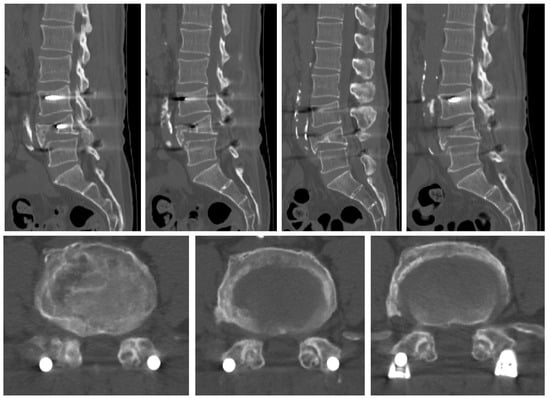

2.2. Case 2